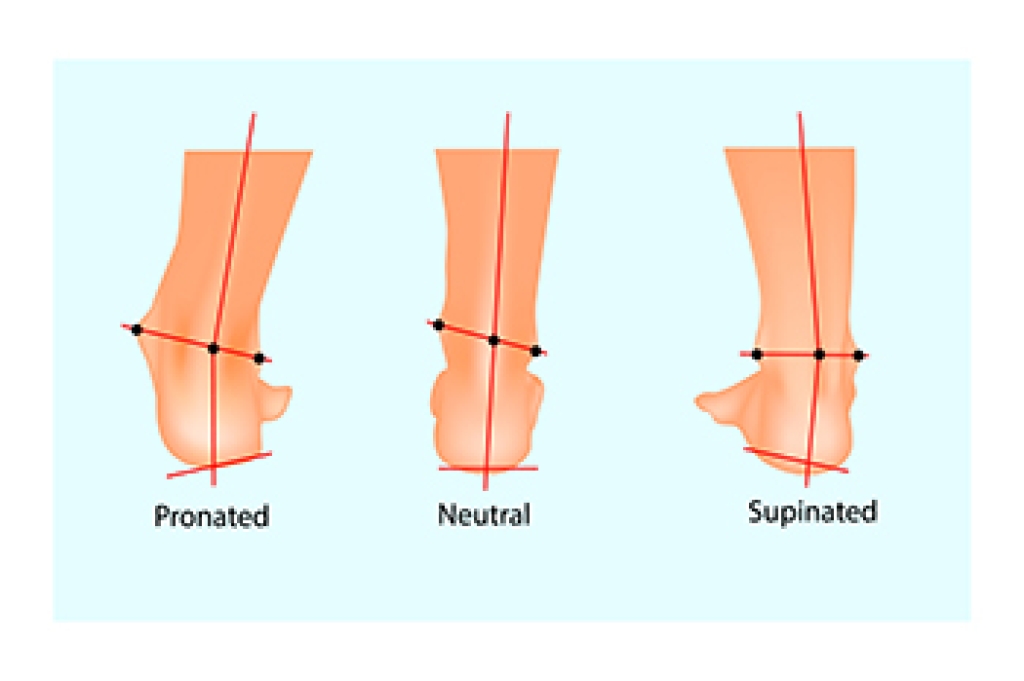

- Wearing shoes that provide good support and cushioning